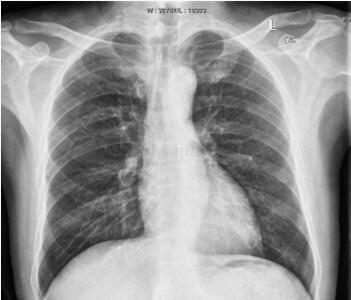

图3‐19‐4 5个月后复查胸片,心影正常大小

5个月后(2011‐3‐2)复查心脏彩超EF59%,各心腔大小及心内结构未见异常;左心室舒张功能减退,收缩功能正常;彩色血流未见异常。

急诊收入ICU,呼吸机无创辅助呼吸,监测心电、血压、呼吸、脉搏氧饱和度。纠正酸中毒、平喘、解痉、抗炎及其他对症支持治疗,患者症状有所缓解。追问病史,患者既往有30年饮酒史,每日饮白酒250g,已戒酒,但发病前又有饮酒史。会诊后诊断为酒精性心肌病、心功能不全转入CCU,予抗凝、抗血小板、减少心肌耗氧、改善心力衰竭、减轻心脏负荷、抑制胃酸分泌、保护胃黏膜等治疗。病情平稳后查心脏彩超提示左心房、左心室明显扩大,LVDd77mm,LAD48mm,左心室室壁运动幅度明显普遍减低,左心室收缩功能明显减低,EF27%。经治疗患者症状明显缓解,可在病房平地步行,无胸闷、胸痛,无心悸、气促。复查肌钙蛋白0.48ng/ml,CK44U/L,CK‐MB42.5U/L。予办理出院,嘱其注意继续服药,门诊随访。5个月后复查心脏彩超示各心腔大小及心内结构未见异常,EF59%;左心室舒张功能减退,收缩功能正常。

患者,老年男性,因突发呼吸困难5小时,加重2小时入院。有吸烟史30年,每日约30支,饮酒30年,每日约饮250g白酒。既往心脏彩超提示左心室、左心房大,左心室弥漫性运动减弱。患者有长期饮酒史,心电图提示心腔扩大,且有左心室肥厚表现,发病前戒酒半年余,本次发病前曾有饮酒史,心脏扩大考虑酒精性心肌病,NT‐proBNP>3000pg/ml,本次急性发病考虑系急性肺水肿、心源性哮喘。患者无典型心绞痛表现,但肌钙蛋白、心肌酶谱升高,考虑与心功能不全心肌损害有关。入院后控制急性心力衰竭后予美托洛尔,维持剂量为95mg,每日1次口服,坚持随访,监督患者戒酒,5个月后复查心脏彩超心功能及心脏大小均正常。